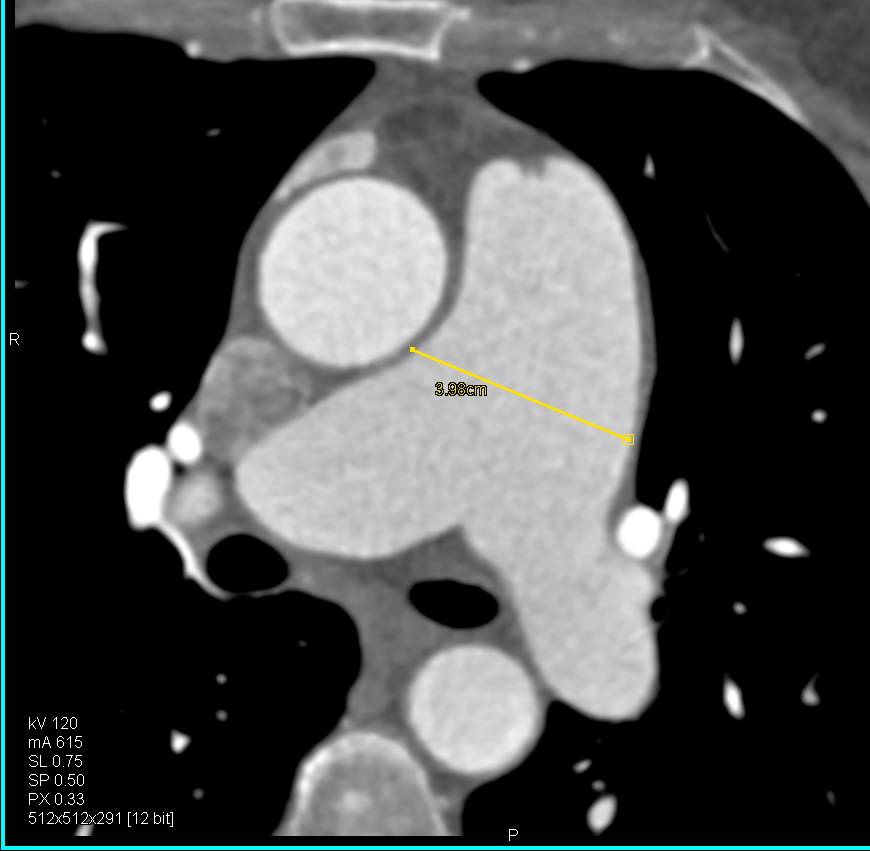

Type A Dissection in Patient with Aortic Valve Replacement